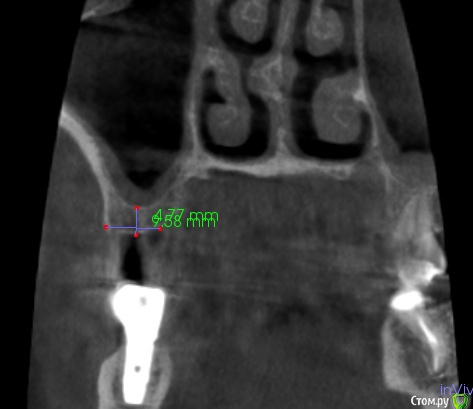

Fin Опубликовано 20 марта, 2020 Поделиться Опубликовано 20 марта, 2020 Здравствуйте коллеги.Планируется имплантация в области 1.6. Но зуб 1.7 с небольшой кистой в гайморовой пазухе, перелечить невозможно СО пазухи в этой области отечна.. Пациенту требуется синус лифтинг. Думаю что нужно удалять 1.7 и после делать имплантацию с ЗСЛ или ОСЛ. На данный момент пациент немного противится, поэтому и решил спросить. Как бы вы поступили, поставили бы короткий имплантат, или ЗСЛ без удаления 7ки. Буду благодарен Вашим ответам. Ссылка на комментарий

Fin Опубликовано 20 марта, 2020 Автор Поделиться Опубликовано 20 марта, 2020 Удалил бы, конечно Тут транскрестально поднять не проблема, не надо короткий, можно даже 10, пожалуй, но зуб этот надо удалять по любым показаниям. Пациент если этого не понимает, то я бы просто отказалПациент вполне адекватный, просто к нам попал после ужасного эндодонтического лечения в другой клинике. Только 2 зуба удалось перелечить, 4 зуба удалили из-за осложнений эндодонтического лечения и уже поставили 3 импланта. А тут еще 4 ка и 7ка на выход просятся. Вот он и просит всеми способами попытаться сохранить до последнего 7ку, а я вас спрашиваю т.к. не вижу другого выхода))Вы бы удалили, через 4 месяца ЗСЛ и пару 5 на 10 поставили? Короткий я не особо хочу, только как вариант. Ссылка на комментарий

Fin Опубликовано 20 марта, 2020 Автор Поделиться Опубликовано 20 марта, 2020 Я бы посмотрел кт в области зуба) может и одномоментно Если отсроченно, то 2 месяца. Но если терапевт не готов на эндодонтию - то удалил бы в любом случае А если терапевт берётся лечить - то я бы подождал две недели после пломбировки и посмотрел симптоматику, дальше закрытым. Если брать винт пошире, то апертура будет почти как латеральная, дно ровное, если пробку костную продавите - поднять несложно. Лечить пытались, не получилось. Не очень понял, вы имеете ввиду поднять имплантом?Я стараюсь вогнутым остеотомом подстукивая продавливать и им же по возможности поднимать, но обычно это до 3-4 мм, больше побаивался.Благодарю за совет. Ссылка на комментарий